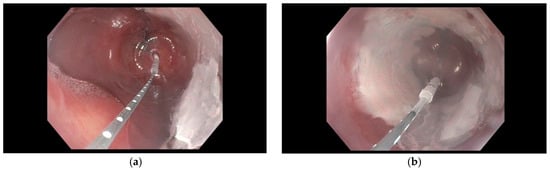

Freeze the Disease: Advances the Therapy for Barrett’s Esophagus and Esophageal Adenocarcinoma

Cryotherapy involves flash freezing of tissue and removing unwanted tissue. Mechanism of injury is causing cell membrane rupture by rapid multiple freeze–thaw cycles, while reserving tissue architecture and the collagen matrix. This promotes favorable wound healing. In recent years, it has gained increasing [...] Read more.

Cryotherapy involves flash freezing of tissue and removing unwanted tissue. Mechanism of injury is causing cell membrane rupture by rapid multiple freeze–thaw cycles, while reserving tissue architecture and the collagen matrix. This promotes favorable wound healing. In recent years, it has gained increasing attention as a treatment option for upper gastrointestinal diseases (Barrett’s Esophagus and early cancer). Currently, two FDA-approved delivery methods are available in the GI tract: Cryoballoon and spray cryotherapy, which will be discussed. In this review, we also propose to examine the expanding role of cryotherapy in gastrointestinal practice, drawing from both clinical studies and illustrative vignettes. In addition, we will highlight its established role in eradicating Barrett’s with low and high-grade dysplasia and compare its outcomes and safety profile with radiofrequency ablation (RFA). We will also discuss the application and safety of spray cryotherapy in the palliation of malignant esophageal strictures when compared with Esophageal stent placement. Cryotherapy may have immunological potential, and it may shrink both primary and metastatic diseases. Ongoing research in this field of Cryo-immunology will be highlighted. Beyond esophageal neoplasia, cryotherapy is increasingly utilized in other upper gastrointestinal precancerous conditions. Through this synthesis, our goal is to provide a timely and comprehensive overview of advancements in cryotherapy and its potential to reshape novel therapeutic approaches in upper gastrointestinal cancers. Finally, we highlight the evolution of a novel platform using nitrous oxide delivered by a handheld device, a contact balloon, and a small replaceable cartridge. This approach may make delivery of cryogen application favorable and a first-line approach in the management of Barrett’s esophagus and early cancer. In addition, Cryoballoon therapy for dysphagia palliation for malignant esophageal strictures may become a preferred approach as more data evolves. Full article

(This article belongs to the Special Issue New Insights in Esophageal Cancer Diagnosis and Treatment)